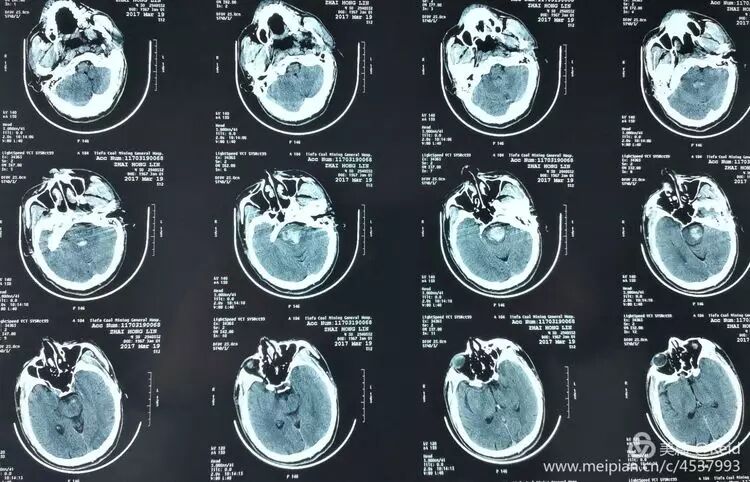

保守治疗72小时后,病情无明显改善,家属决定尝试外科手术干预,谨慎沟通后,以移动呼吸机辅助下,经CT引导精确定位置管手术。

术中将外径3.0mm的细引流管经乙状窦后小脑中脚(脑桥臂)植入桥脑血肿内,术中抽出1-2ml陈旧血肿。术后尿激酶注入融化固体血肿。

术后第5天复查头CT显示桥脑血肿清除满意。